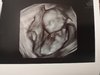

Mam już 3 dzieci a to moja 5 ciąża (stąd moje obawy czy mnie zaakceptujecie) Po 3 ciąży brałam tabletki anty ponieważ nie chciałam więcej dzieci.Niestety w marcu dopadło mnie straszne choróbsko. Najpierw zapalenie krtani, potem płuc. Brałam 3 różne antybiotyki a przez myśl mi nie przeszło że któreś może osłabić działanie tabletek anty. W kwietniu okazało się że jestem w ciąży. Był to dla mnie szok, ale z czasem pokochałam tą istotkę. Niestety na wizycie 18 tc usłyszałam że mojemu synkowi nie bije serduszko ( później okazało się że miałam niewydolność łożyska). Strasznie to przeżyliśmy. Dlatego jak dostałam zielone światło od lekarza, zdecydowaliśmy z mężem, że nie będziemy się zabezpieczać i co ma być to będzie. Dziś jestem w 14t3d. Najprawdopodobniej to córeczka